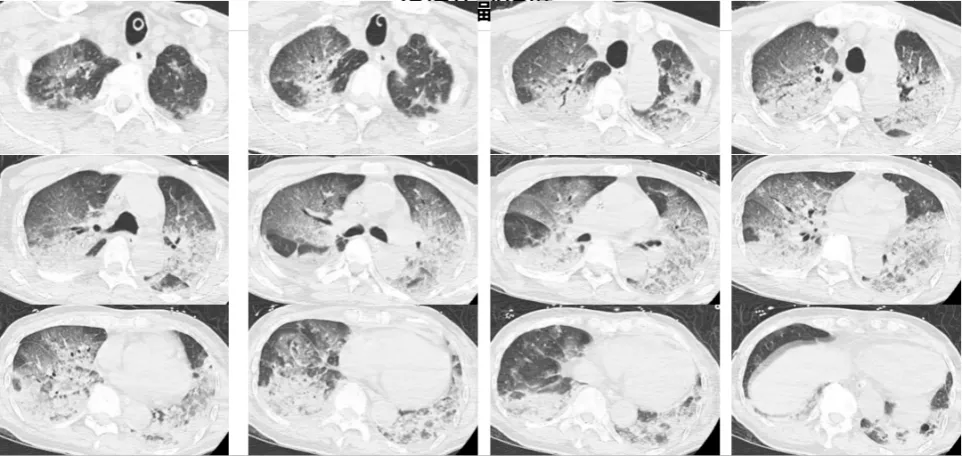

2024年12月,浙江杭州的韓爺爺午飯后去洗浴中心蒸桑拿,沒多久就昏迷并口吐白沫,送醫(yī)檢查發(fā)現(xiàn)雙肺大面積變白,確診為熱射病誘發(fā)的肺水腫。這一案例警示我們,冬季溫暖密閉環(huán)境的風(fēng)險(xiǎn)不容小覷。